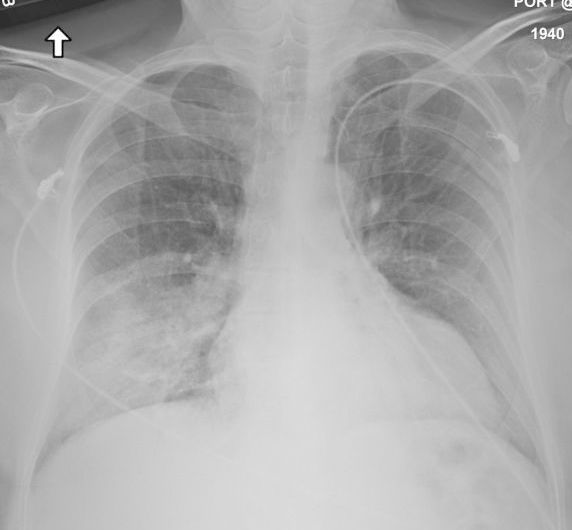

MERS患者の肺炎を示すX線写真